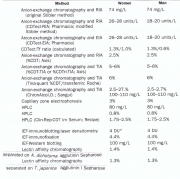

| 16:57, 29 בפברואר 2016 | Cdt2.png (קובץ) |  |

826 קילו־בייטים | Motyk | 1 | |

| 22:24, 28 בפברואר 2016 | Cdt1.png (קובץ) |  |

531 קילו־בייטים | Motyk | 1 | |